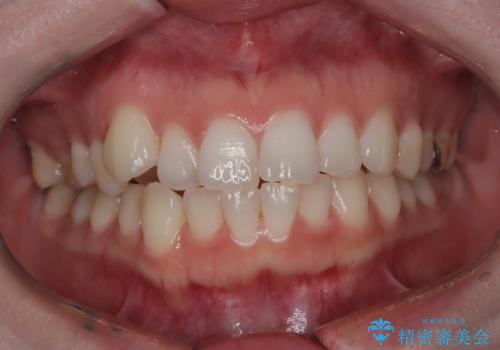

- 20代女性

- 右上の八重歯と歯並びのデコボコを気にされて来院されました。精密な検査の結果、歯列のスペースがわずかに不足していることが判明。患者様の「抜歯を避けたい」というご希望を最大限に尊重し、アンカースクリュー(TAD)を用いて奥歯(臼歯部)全体を後方へ移動させることで、八重歯が並ぶスペースを確保する治療計画を立案しました。装置にはワイヤー矯正を使用し、確実で効率的な歯の移動を目指します。

今回のワイヤー矯正治療では、抜歯せずに歯を並べるスペースを作るため、特殊な小さなインプラントであるアンカースクリュー(TAD)を一時的に使用しました。このアンカースクリューを固定源として、奥歯(臼歯部)全体を後方へ遠心移動させました。従来の矯正では難しかったこの奥歯の移動を確実に行うことで、前歯の八重歯を適切な位置に並べるスペースを確保。治療の結果、抜歯することなく右上の八重歯と叢生が解消され、機能的にも審美的にも整った美しい歯並びを獲得していただけました。